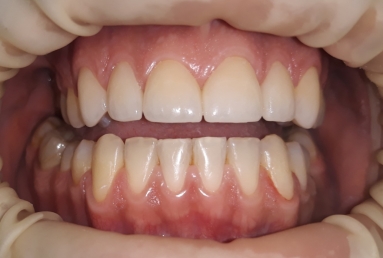

The final porcelain veneers for all frontal maxillary teeth are completed with tooth whitening and changing some composite fillings in lower frontals. On the lower left side a dental implant is inserted, on the upper right side external sinus lift is done. the treatment will be finalised with another upper implant, then two crowns on implants.